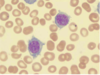

Chronic Lymphocytic Leukemia (CLL)

Chronic Lymphocytic Leukemia (CLL)

Hairy Cell Leukemia

Hairy Cell Leukemia

Hairy Cell Leukemia